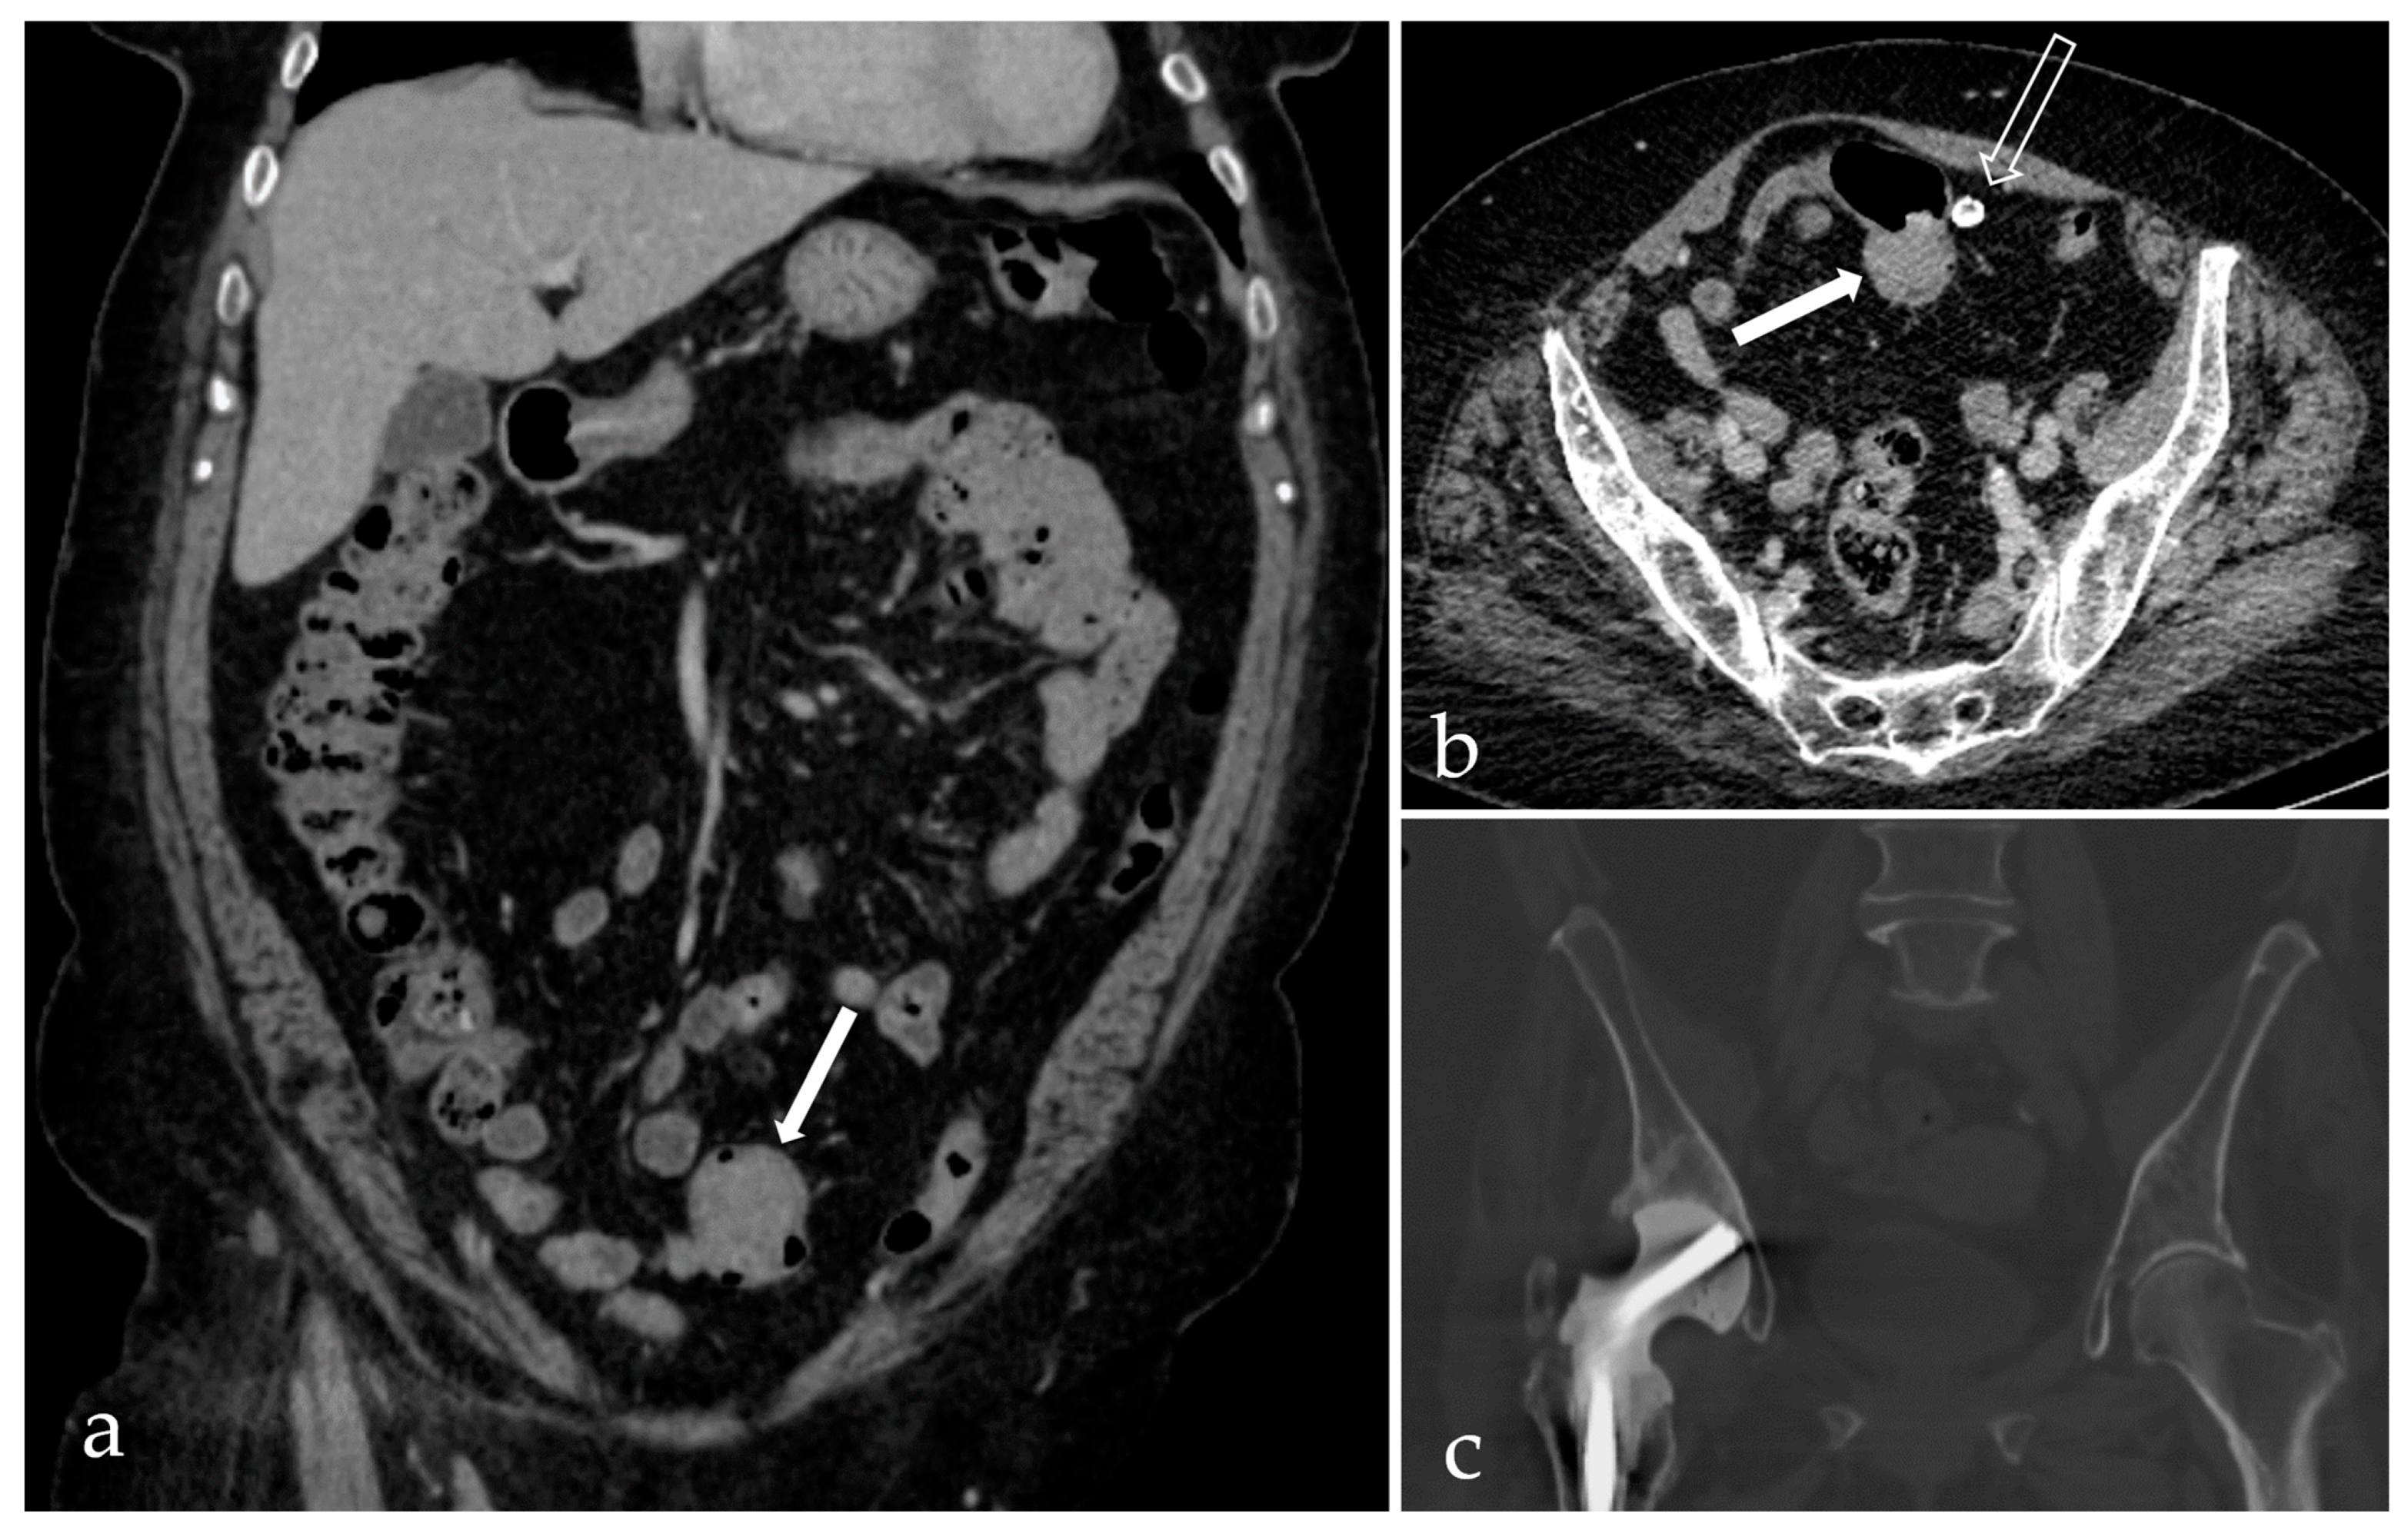

2. Case Report